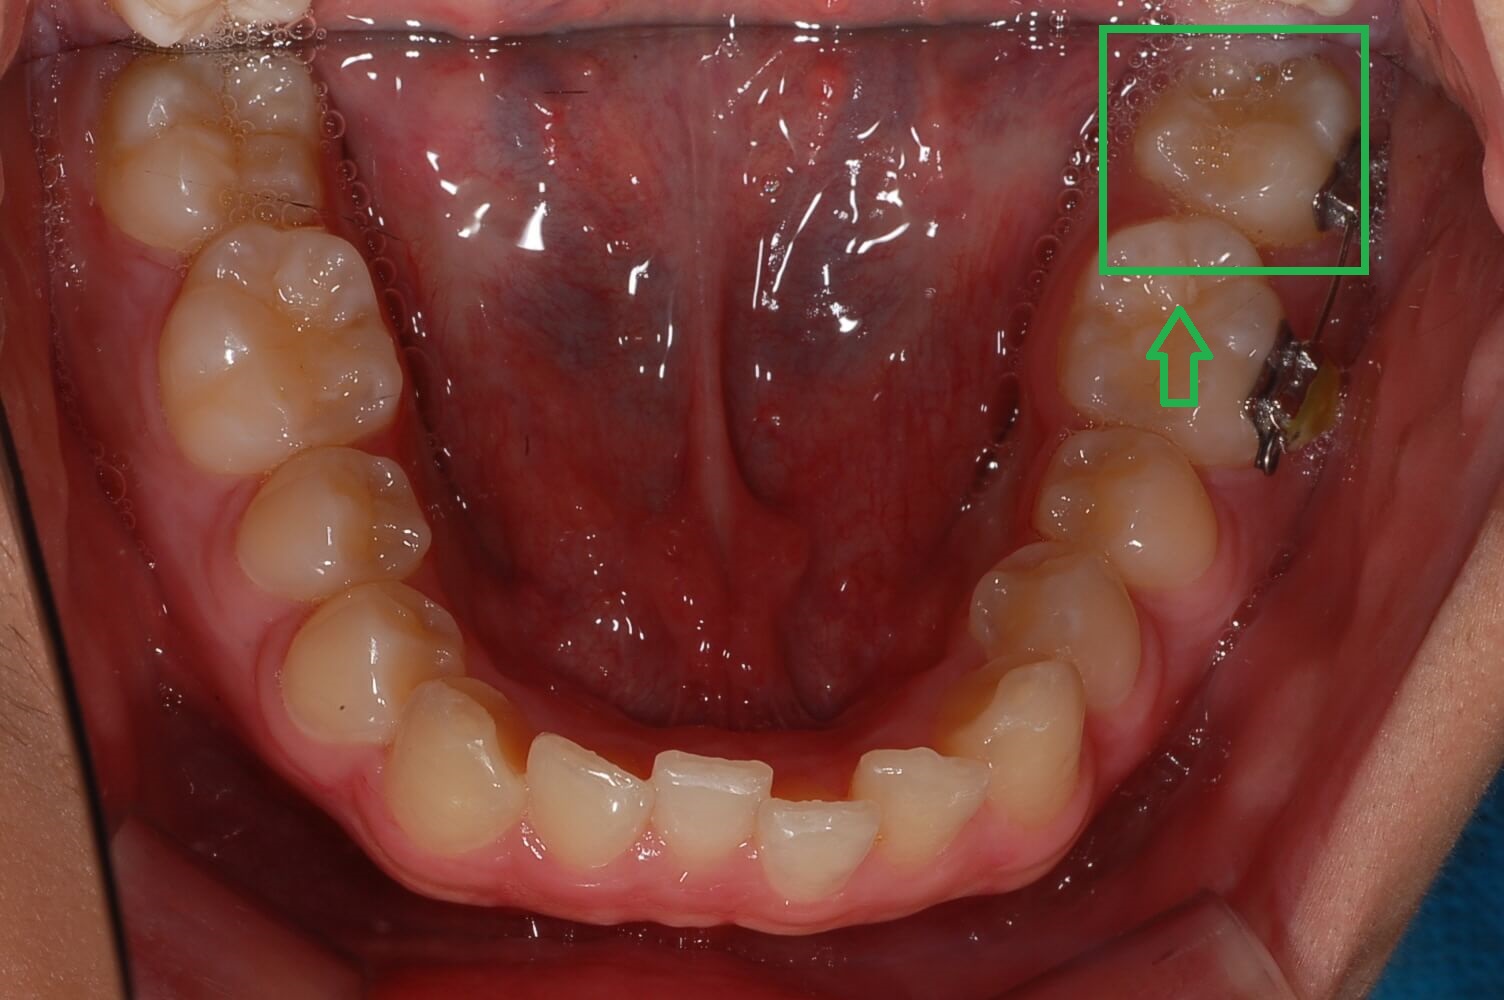

◎ 아들치아교정 전 상태확인 (가위교합사진)

- 「윗 어금니 가위교합 1개」

- 「아래 어금니 가위교합 1개」

저는 치아가 자유로이 움직인다는 것을 처음 알았습니다. 그리고 복원력이 있다는 것도 알게 되었는데요. 사진에서 보듯이 어금니가 옆으로 누워있습니다.

위, 아래 어금니가 모두 그렇는데 아래 어금니는 브라켓 설치로 힘을 주어 잡아당기고 있고 윗 어금니는 스크류를 박고 고무줄(체인)로 잡아당기고 있습니다.

▼ 아래 어금니 블라켓으로 고정후 힘을 주어 당기고 있는 모습

▼ 윗 어금니는 스크루를 박고 체인으로 묶어서 한 단계씩 줄여나가면서 이동시킴.